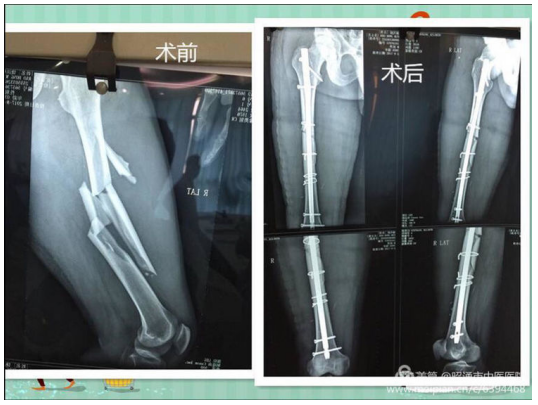

近日,骨伤科收治2名复杂粉碎性股骨干骨折患者,出血严重并伴有失血性休克表现,如不及时进行有效的救治,既会因失血性休克危及生命,又会导致严重的下肢残疾。

经科室认真讨论研究,拟对2名患者行桥接系统、髓内钉内固定系统手术,相比传统切开复位钢板螺钉内固定术,该技术具有创伤小、出血少、中心固定牢靠等优势,对于复杂粉碎性骨折具有很好的治疗效果。在科室医务人员的精心诊治和护理下,术后患者恢复情况较好。(通讯员/骨伤科 罗健飞)